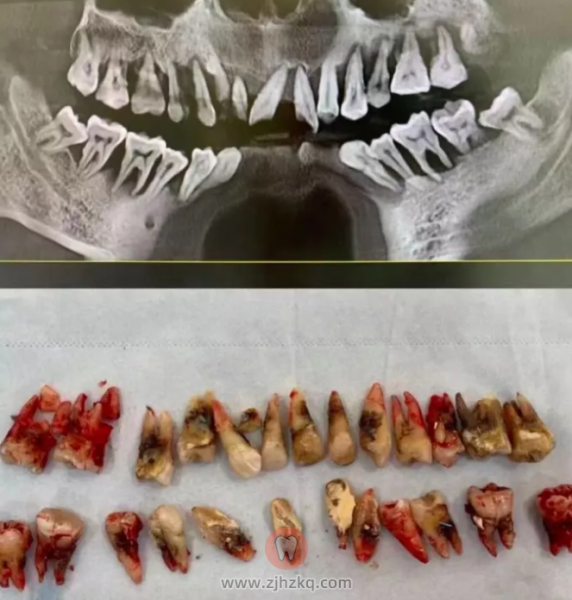

徐勇刚曾在其公号发文介绍,一个30多岁的小伙子,只是因为“牙齿松动”来就诊。但等待他的,却是晚期牙周炎患者的最终归宿——全口牙松动、拔除。